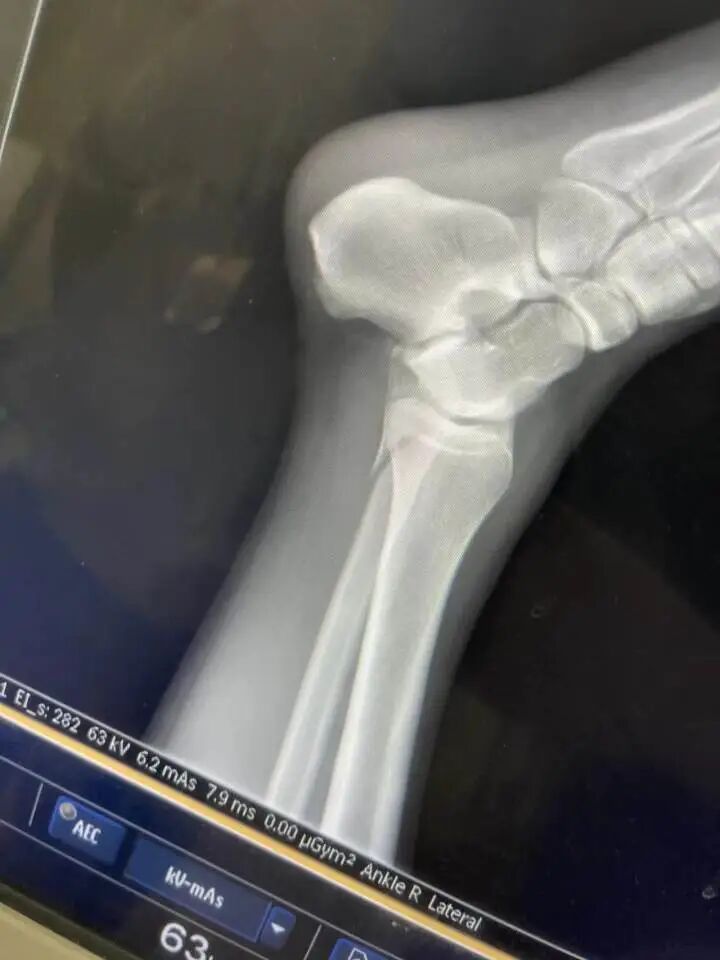

“我感觉是水比较浅,水下有个不平的东西,当时一瞬间还没感觉,脚崴了,只好硬撑着走,走上岸就走不动了,脚已经使不上劲儿了。最后用一只脚蹦到救护车上。”

“我就把躺的位置让给她,她的腿骨折了,我是踝骨受伤。现场的工作人员让我们到二级以上的公立医院治疗,然后报销。”

“医院建议我动手术,我当时打算,先保守治疗吧,因为自己还年轻,不能因为这点事儿动刀。”

小黄说,自己落水受伤后,腿已经肿起来,动不了。自己花钱雇救护车回到了无锡,昨晚没睡着,好疼。

“从场地送到医院救护车的钱,都是我和小董一人一半自己付费的,连治疗费用都是我们自己垫付的。”